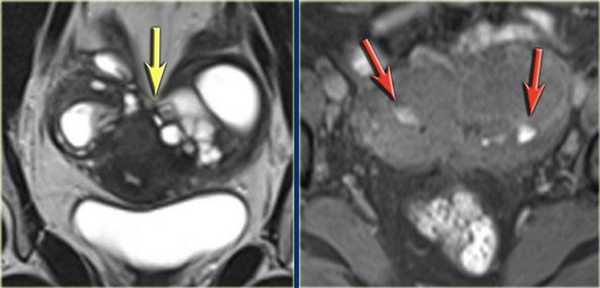

На Т1 и Т2 взвешенных томограммах у пациентки с эндометриозом визуализируются «целующиеся» яичники, расположенные вплотную друг к другу из-за множественных спаек. Также видны небольшая геморрагическая киста в левом яичнике и поверхностная геморрагическая бляшка, дающие гиперинтенсивный сигнал (красные стрелки)